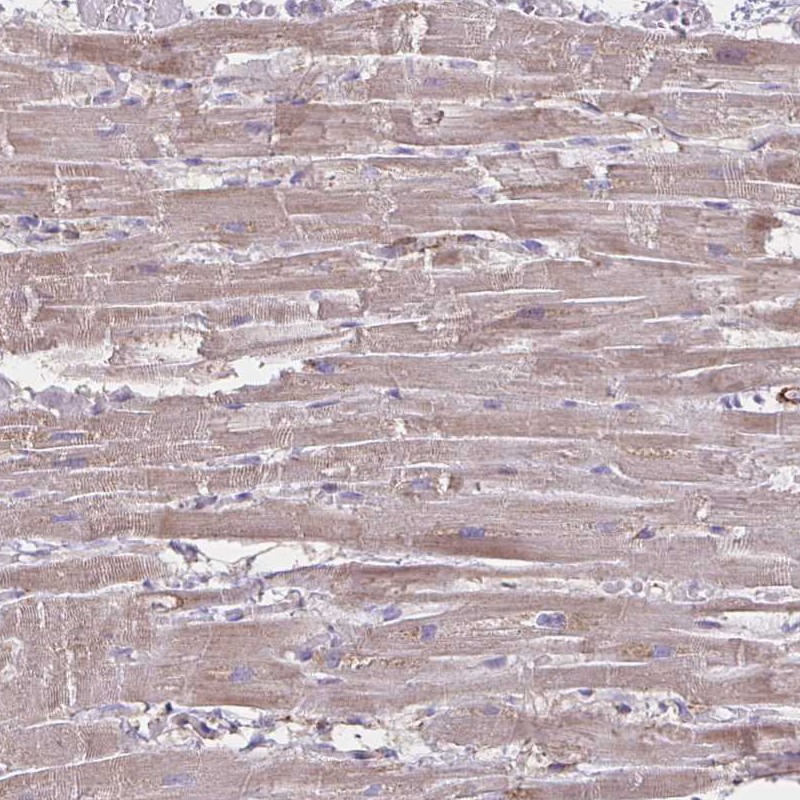

Immunohistochemical staining of human heart muscle shows moderate cytoplasmic positivity in myocytes.